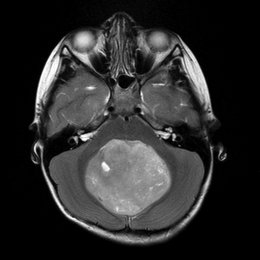

PREGUNTA 3 de 10

¿Cuál es el diagnóstico más probable de la siguiente imagen?

A)

quiste aracnoideo

B)

Quiste de la bolsa de Rathke

C)

craneofaringioma

D)

Silla turca vacía

E)

macroadenoma hipofisario